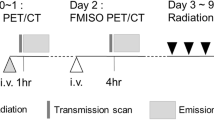

Patients received a total dose of 60–66 Gy in 30–33 fractions with 3-DCRT. The median dose received for the 12 patients was 66 Gy. Two separate plans using the CT-GTV and the PET-CT-GTV were generated, and patients were treated using the PET-CT-GTV plan. The pilot study investigated the technological feasibility of this method. The Phase II study was a two-stage phase II study to evaluate its safety.

The planning CT was done with the patient in the standard supine position with lung board and kneefix immobilisation. Reference set-up marks were tattooed at CT. The planning PET/CT was the same position, with patient aligned to tattoos using lasers. Safety checks were essential from a radiation protection perspective and were performed to ensure that the PET/CT scan could be acquired prior to injecting the patient. The possibility of the patient colliding with the gantry was checked and eliminated, and the patient’s ability to tolerate the enclosed scanner was confirmed. The patient was then injected with FDG. The PET/CT scan (the hot session) was acquired 1 h after the injection. The radiation therapists were responsible for establishing the patient into the correct treatment position and for the acquisition of the CT scan. The diagnostic radiographers were responsible for the PET capture. All contouring was done on Advantage Sim Workstation.

Separate plans based on the CT and PET/CT volumes were generated. The minimum prescribed dose of radiation was 60 Gy at 2 Gy per fraction. Ninety-five percent of the dose covered 100% of the PTV for both CT and PET/CT plans. The patient was subsequently treated using the PET/CT plan.